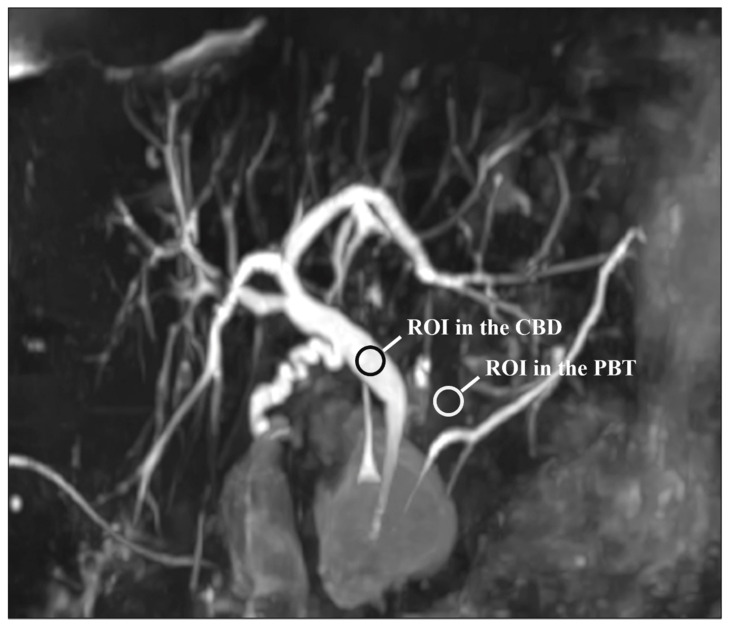

For each patient and each sequence, a representative section of the CBD was selected. Then, circular regions of interest (ROIs) were traced on the CBD and PBT and the mean signal intensities were recorded. The CBD ROI was at least 5 mm² and was placed in a uniform artifact-free region in the middle of the duct. A similar ROI was positioned on the peri-CBD tissues, avoiding artifacts and fluid-containing structures. Note that the ROIs were drawn on the native images. Figure 1 shows the ROIs placement. The CR was estimated using the following formula [ref. 23,ref. 29,ref. 30]:

CBDPBTCBDPBT

where CR is the estimated contrast ratio, SICBD and SIPBT are the mean signal intensities of the CBD and the PBT, respectively.